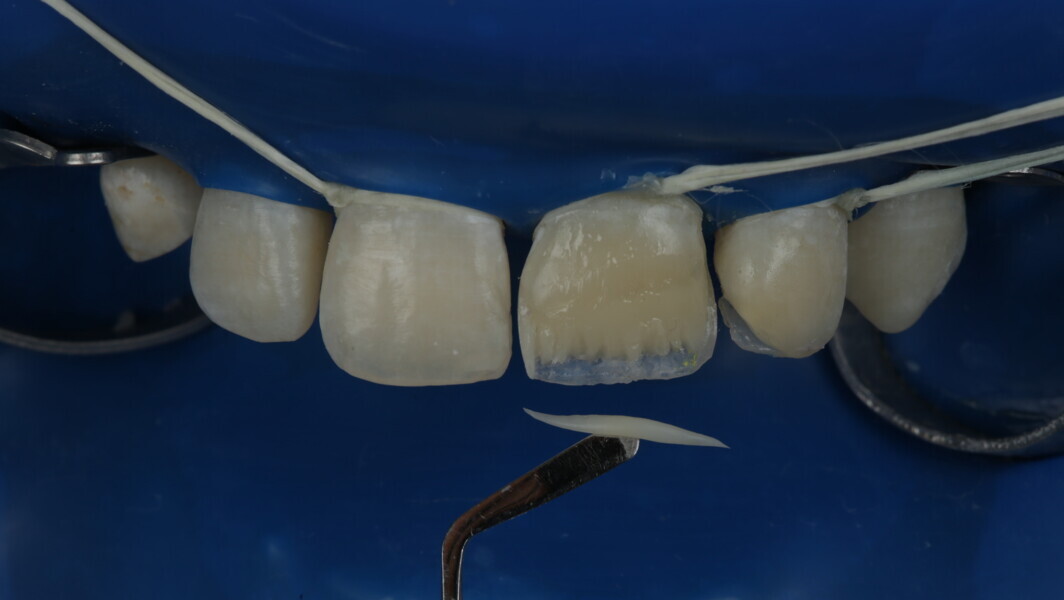

A 10-year-old male patient reported with a complaint of trauma to the upper left central and lateral incisors, involving the enamel and dentin. Direct composite was used in multi-layers and the smile was restored. This article explains detailed steps in the polychromatic layering technique with special emphasis on the finishing and polishing protocol. 3M Espe Filtex Z350 Xt was used with a universal bonding agent.

Fig 1-7: Evaluation and mock up

Fig 8-18: Bonding and palatal shell

Fig 19-24: Contact build-up with band and wedge

Fig 25-30: Layering protocol step by step